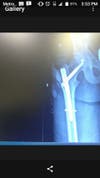

I'm looking for a witness to see if anyone was in the intersection of Murrieta and olivina in Livermore CA on March 8 2017 at about 5:50 to 5:55a.m I was crossing the street in the crosswalk on my longboard and had the greenlight when I was struck on my right side of my hip breaking my pelvis and I ended up being in hospital for 3 days and getting surgery which caused me to have a titanium plate in my hip, putting me out of work to support my girlfriend and two children. The description of the car is a 2005 or 2006 Nissan Altima similar to vehicle in picture above he was traveling from direction of olivina when he struck me in crosswalk on Murrieta if anyone has any information to help me or if the driver himself wants to man up and help me confessing I deeply appreciate it was a male Hispanic late 30s early 40s average body type about 5 "10 dark hair, obviously in a hurry. I jumped up fast after being hit cause that's what skaters do . the man got out of his car asking if I was ok and claimed he didn't see me.. but I was in shock so I was honestly just trying to get away from the front of his car then I replied I don't know he told me sorry then bailed out watching me limp as he drove away ,about 15 feet down the sidewalk I collapsed and realized it was more serious then it felt at first if anyone has any information please email me at jw540bsts@gmail.com if you know anyone with surveillance in the area or license plate, vehicle most likely lives in the area of olivina on the McDonald's half near falcon way